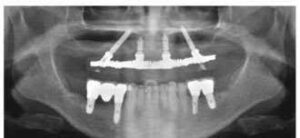

All on Four: O Que É, Como Funciona e Quais os 5 Benefícios?

O que é a técnica All-on-Four? A técnica All on Four é um procedimento inovador de reabilitação oral que permite a colocação de uma prótese